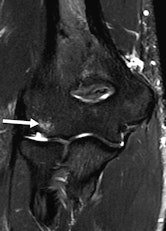

"Elbow injuries in Olympic sports have not been reported previously," noted lead author Dr. Sarath Bethapudi, from the department of musculoskeletal radiology at Leeds Teaching Hospitals National Health Service (NHS) Trust in the U.K. "Most of the injuries resulted from valgus strain with hyperextension of the elbow and usually presented as injuries to the medial joint supporting structures. Combinations of medial and lateral ligaments were seen in combat and power sports with high-energy acute trauma. Such injuries also resulted in tears to secondary stabilizers of the medial joint, including the common flexor tendons and medial muscular compartments" (AJR, September 2013, Vol. 201:3, pp. 535-539).

Of the 28 elbows scanned for acute sports injuries, 15 had high-grade ligament injuries, and 12 of these ligament injuries occurred in contact sports and weightlifting. The remaining three injuries were seen in throwing athletes, two of whom were javelin throwers and one of whom was a volleyball player.

"Tears of the common flexor and extensor tendons occurred in combination with ligamentous injuries. This occurs because common flexors and extensors act as secondary stabilizers of the elbow joint and are injured when the primary stabilizers fail. Once again, these injuries occurred primarily in combat sports, weightlifting, and overhead-throwing athletes," stated Bethapudi, who was responsible for data collection and analysis at the 2012 Olympics and has received funding from GE Healthcare, a sponsor at the games.

Significant ligament and tendon injuries to the elbow can occur often in nonthrowing athletes, and most of the elbow injuries seen in these athletes were isolated high-grade ulnar collateral ligament (UCL) injuries, although combinations of medial and lateral ligament injuries can occur, the authors concluded. Ulnar attachment tears were the next most common injuries, followed by midsubstance tears of the UCL. This trend differs from the existing literature, which suggests that midsubstance tears are the most common type of UCL injuries, they wrote.